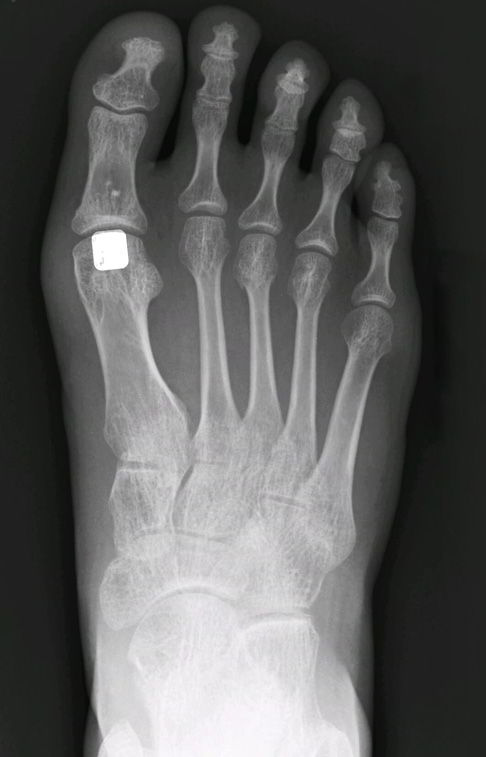

Eine Großzehengrundgelenks-Hemiprothese kann eingesetzt werden, wenn eine endgradige Arthrose am Großzehengrundgelenk besteht. Klinisch wird diese Erkrankung vorerst durch einen eingeschränkten Bewegungsumfang, Einsteifung und erschwertem Abrollen des Fußes sowie stechenden Belastungsscmerzen bei Bewegung der Großzehe deutlich.

Diese krankhafte Veränderung kann zu einer vollständigen, schmerzhafte Versteifung des Großzehengrundgelenks führen, die häufig von Entzündungszeichen wie Schwellung und Rötung des darüber liegenden Gewebebereichs begleitet wird.

Um feststellen zu können, ob für einen Patienten eine Hemiprothese für den Hallux rigidus geeignet ist, wird eine klinische und radiologische Untersuchung durchgeführt. Wenn Schmerzbeschwerden bestehen, erfolgt eine Abschätzung des Arthrosegrades. Wenn eine Arthrose als Ursache für die Beschwerden festgestellt wird, darf diese ein gewisses Stadium nicht überschreiten, um sie mit einer Hemiprothese versorgen zu können. Eine sehr fortgeschrittene Arthrose mit Zerstörung an beiden Gelenkflächen stellt eher eine Indikation für eine Totalendoprothese oder eine Versteifung des Gelenks dar.

Die Operation beginnt mit der Öffnung des Gelenks durch einen etwa 3 cm langen Schnitt auf der Oberseite der Großzehe. Anschließend werden alle Knochenauswüchse (Osteophyten) am basalen Gelenkteil entfernt (Cheilektomie). Durch leichten Zug an der Großzehe, kann der Gelenkspalt dargestellt und zur Behandlung freigelegt werden.

In das Grundglied der Großzehe wird eine Vertiefung zur Verankerung der Oberflächenersatzprothese angebracht. Am gekürzten, knöchernen Ende des Grundglieds wird die optimale Größe der Hemiprothese bestimmt und mit dem Pressfitverfahren befestigt. Nach Überprüfung des Bewegungsumfangs der Prothese wird der Schnitt mit einer Naht verschlossen.